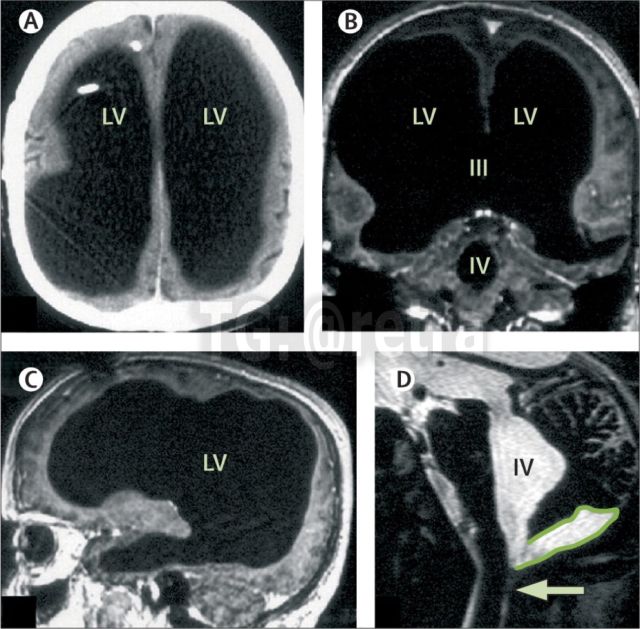

Back in 2016, a 44-year-old man went to the hospital with weakness in the leg. But during the examination, something very strange. His skull was full of fluid, and only a thin layer of brain brain tissue. Roughly speaking, the Frenchman did not have 90% of the brain, but at the same time he lived a normal life. The man has a family and a normal job. His IQ was 84, which is slightly below average. Doctors noted that he does not have high intelligence, but at the same time the French socially adjusted, despite the fact that he lacks most of the brain.